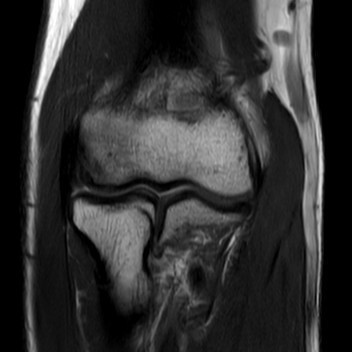

下の写真1は臨床機3テスラ(磁場の強さ。ごく単純にいえばこれが強ければ強いほど高い信号が得られます)MRIを使った肘の画像です。現在日本(世界)で最高水準の画像です。ちょうど真ん中に隙間がありますが、これが関節腔で、ここを中心に曲げ伸ばしができます。向かって上側が上腕といって肩に近いほう、向かって下側が手に近いほうです。

写真1 最新の臨床機による画像